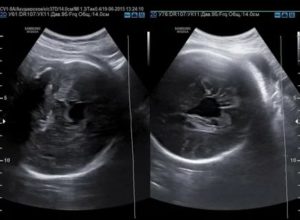

- УЗИ;

Однако есть опасность того, что мутные околоплодные воды при беременности являются следствием развития инфекции. Чтобы подтвердить или опровергнуть этот факт, необходимо перестраховаться и пойти повторное УЗИ, оценив при этом количество и состав вод. Можно сходить на прием к другому врачу и пройти исследование на другом аппарате.

Для контроля врачи пользуются показатель амниотической жидкости, который подсчитывается во время УЗИ. Если его индекс превышает табличные пределы, то диагностируется многоводие.

На УЗИ диагност может увидеть увеличение высоты дна матки, а также активизацию плода. На плановом осмотре врача может насторожить высокая плотность матки при пальпации, глухое сердцебиение плода.